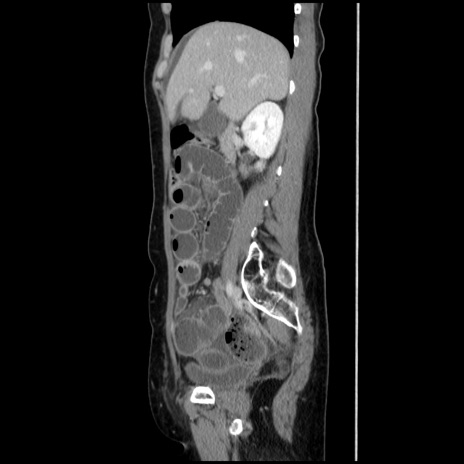

冠状断像

【症例】40歳代 女性

【主訴】上腹部痛、嘔気・嘔吐

【現病歴】約9時間前頃から急に上腹部痛、嘔気、嘔吐が出現。改善しないため救急要請。

【既往歴】子宮頚癌(広汎子宮全摘術、放射線療法)、腸閉塞

【身体所見】腹部:平坦、軟、腸雑音亢進、上腹部を中心に腹部全体に圧痛あり。

【データ】WBC 8400、CRP 0.03